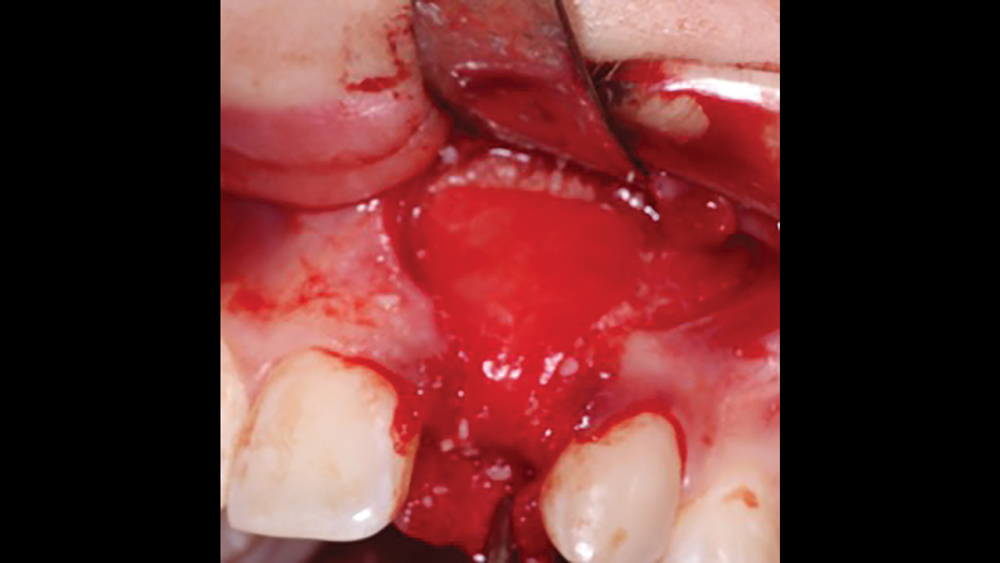

Platelet-Rich Fibrin

The use of platelet-rich fibrin (PRF) is increasing in popularity for GBR procedures (Figs. 10a–10d). This second-generation platelet concentrate has the advantages of lower cost, no need for additional reactive agents, and a higher concentration of platelets in comparison to platelet-rich plasma. The PRF protocol involves the centrifuging of the patient’s whole blood, resulting in the formation of three layers. The bottom layer contains red blood cells, which is discarded; the top layer is clear-colored and is termed platelet-poor plasma; and the middle layer, which is the fibrin matrix, is used as a membrane in bone regeneration procedures.

Figure 10a Platelet-rich fibrin

Figure 10b Platelet-rich fibrin

Figure 10c Platelet-rich fibrin

Figure 10d PRF membrane is placed

Figures 10a–10d: Platelet-rich fibrin has the advantages of lower cost, no need for additional reactive agents, and a higher concentration of platelets in comparison to platelet-rich plasma. Shown, a venipuncture was performed to obtain approximately 10 cc of blood (10a). The platelet-rich fibrin is obtained (10b), followed by modification of the fibrin clot into the membrane (10c), and then the PRF membrane is placed (10d).